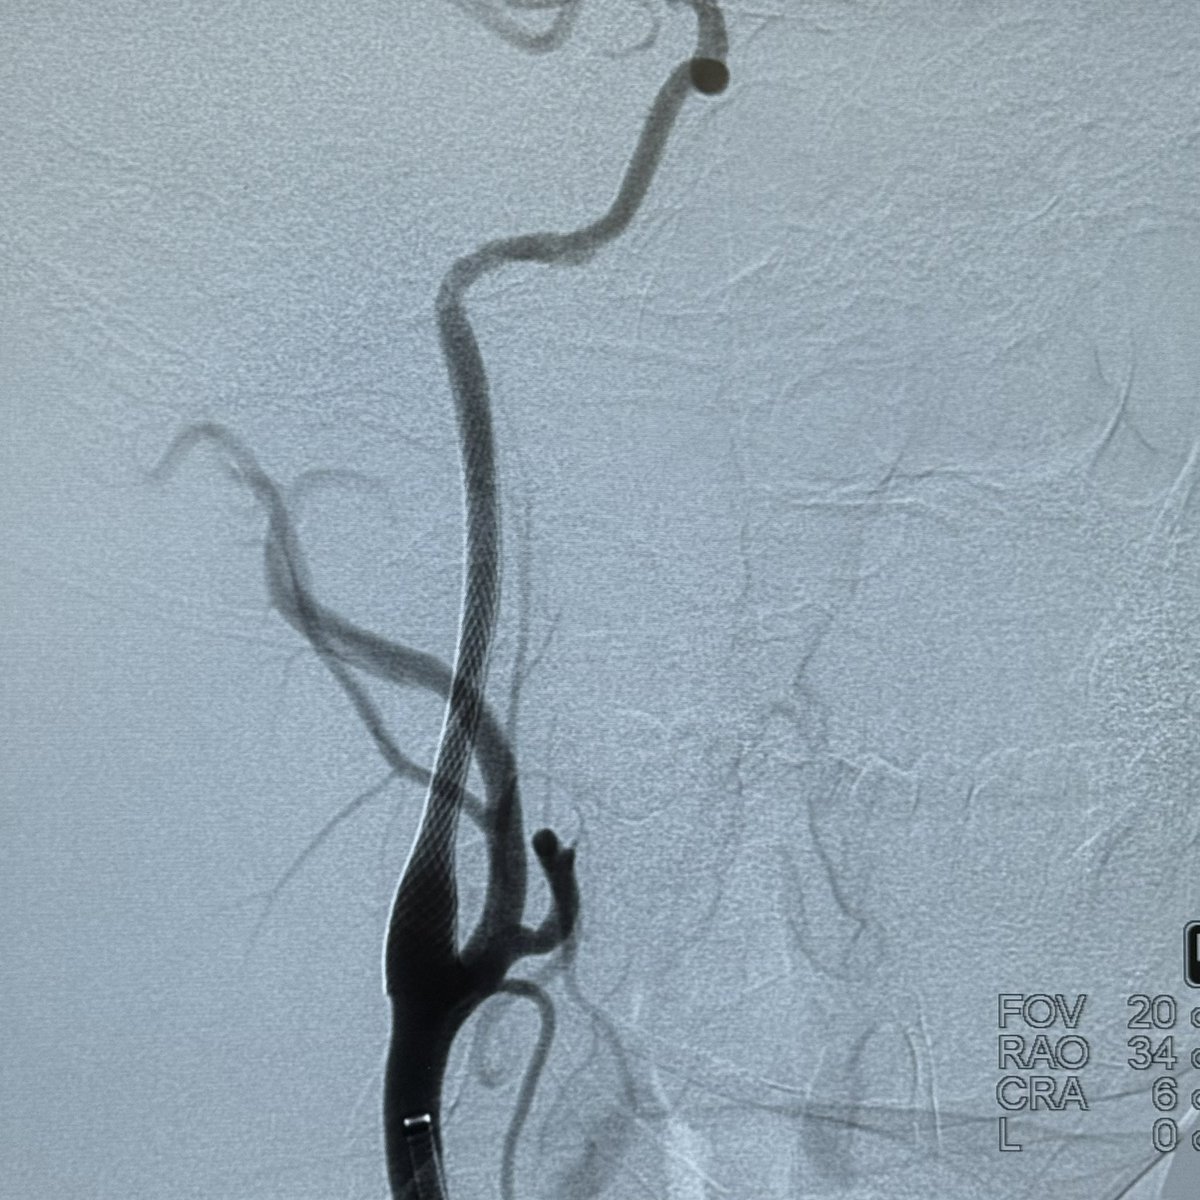

The Patient presented with recurrent episodes of loss of consciousness, DSA revealed extremely severe stenosis of the basilar artery. Under local anesthesia, a self-expanding drug-eluting stent was implanted via the radial approach. Postoperatively, the BA exhibited mild residual stenosis, and the patient's overall condition was satisfactory.

Long-term follow-up results are eagerly anticipated.

@daigaole Great case!

Do you continue with antiacoagulation or antiagregation?